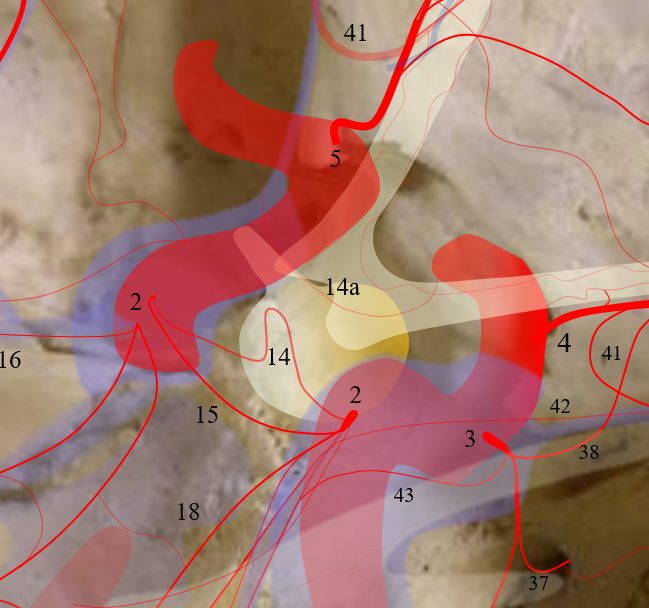

14a above — a very rarely seen by Digital Subtraction Angiography, but much more commonly with Cone Beam / Flat Panel CT, tiny vessel or vessels arising from the “hypophyseal” segment of the internal carotid artery — a proximal intradural segment also known as supraclinoid, paraophthalmic, etc. See ICA page for details of this semantic disorder.

The artery arises from the medial carotid wall — pituitary is medial to the carotid — and supplies the hypophysis, by definition — the pituitary — usually anterior hypophysis and pituitary stalk. The inferior hypophyseal arteries (from the MHT) are usually much bigger and supply the posterior pituitary.

The “hypophyseal aneurysm” — a medially or inferiorly projecting aneurysm from the hypophyseal segment — is thought to be related to this branch — at least by those who believe that aneurysms must arise from branch points. Aneurysms, of course, don’t care for our opinions, but we are right more often than not.

If you want to see hypophyseal arteries, do some high res DYNA of VASO imaging. Because of superimposition over the carotid in lateral views, again, its hard to see. Below is an example of why this artery, always there (always, yes! — occlusion is pathologic always such as athero) depends on technique